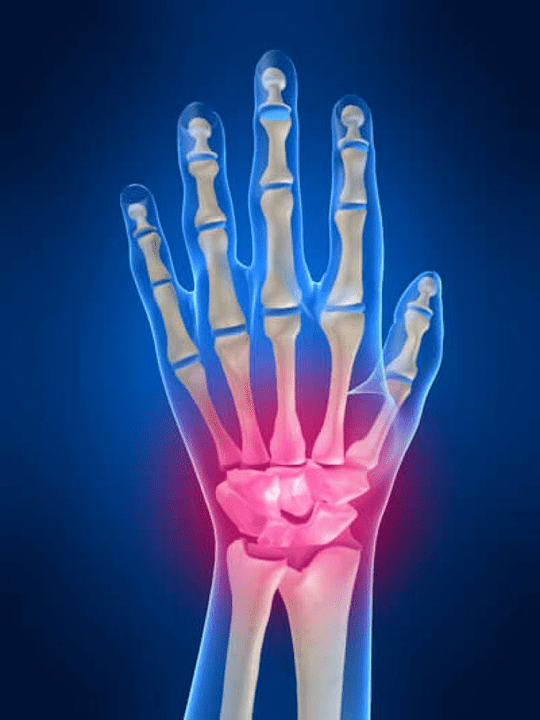

Anatomie der Handverbindungen

Alle Handverbindungen sind üblich, um in die folgenden Gruppen unterteilt zu werden:

- Handgelenk Joint;

- Gelenke des Handgelenks;

- Kartellverbindungen;

- Interpencial -Gelenke;

- Parlemonal-Phalanx-Gelenke;

- Interphalanxgelenke.

Das Handgelenk Joint